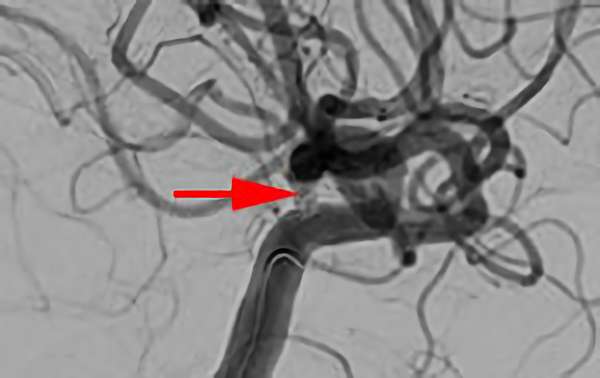

No.1631 手術中